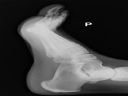

Skręciłeś staw skokowy, bardzo popularny uraz. Zalecam wizytę u lekarza, i bardzo możliwe, że potrzebne będzie rtg. W większości przypadków wystarczy bandaż z altacetem - w poważniejszych usztywnienie gipsem.

Ja tam widzę wyraźne zaciemnienia szpiku kości piętowej. To z pewnością ostra białaczka monoblastyczna z przerzutami na węzły przyuszne jego psa. Zalecaną kuracją jest napromieniowanie ogórkami z Fukushimy i inhalacje oparami palonej bawełny w Instytucie Samoodnowienia Człowieka prof. Norbiekowa.